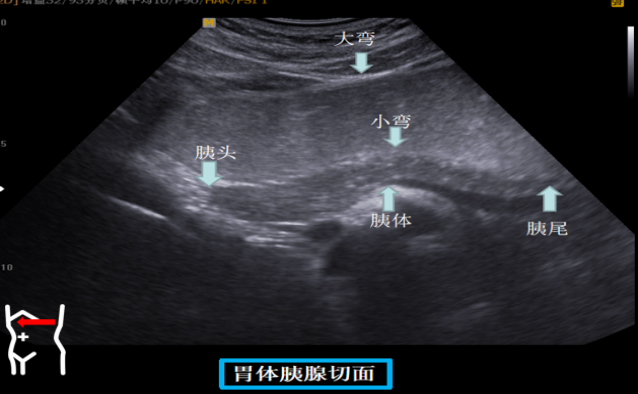

第三组胃体切面

患者取右侧卧位探头从左肋缘下朝左上方翘找出脾下缘以其为起点原位逆时针扇扫依次可见胃底贲门胃体长轴短轴胃体胰腺胃角长轴胃角短轴胃角切迹是胃体与胃窦分界这组切面同时可以观察到胃窦有时还可以观察到球部。